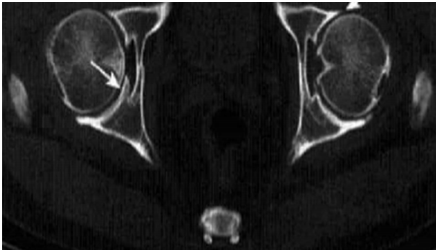

骨关节炎 (osteoarthritis.OA)是关节软骨的退变和继发性骨质增生的一种慢性关节疾病,又可称为骨关节痛、骨关节病、老年性关节炎、增生性关节炎、萎缩性关节炎、肥大性关节炎、软骨软化性关节炎节病等。多见于中老年人,其发病率与年龄增长呈正相关。全世界范围内估计,60 岁以上的 9.6%的男性和 18.0%的女性有骨性关节炎症状。并且骨性关节炎主要影响承重关节。骨关节炎主要有两大临床特征,分别是退化以及增生。退化包括了关节软骨纤维化和退化,韧带松弛,关节周围肌肉萎缩等;增生则包括了骨赘形成、软骨下骨硬化、滑膜组织增生、关节囊增生等。骨关节炎的治疗目的是缓解疼痛,延缓关节软骨退变,改善生活质量。在治疗过程中,临床医生常使用非甾体消炎药、氨基葡萄糖等药物。

二甲双胍具有“神药”的称号,在以往常常被用来治疗2型糖尿病、抗衰老,但,随着对二甲双胍这一的研究不断深入,发现其对骨关节炎也具有不错的效果。二甲双胍对正常年轻的关节软骨细胞有抑制其增殖分化,延缓其成熟老化,而对于已经老化无分化能力的软骨细胞,则通过增加自噬,延缓 OA 进展。二甲双胍对 OA具有双重保护作用:早期能延缓软骨细胞老化,晚期能促进软骨细胞自噬,避免 OA 进展。